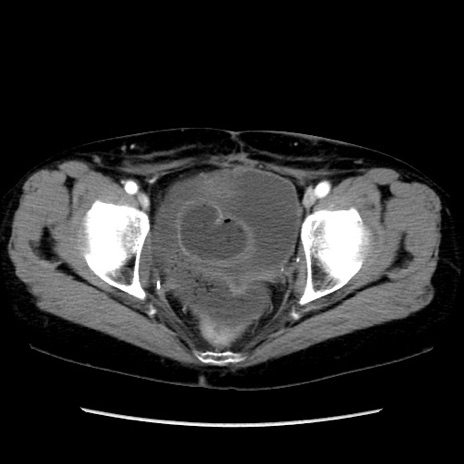

症例32(横断像)

【症例】40歳代 女性

【主訴】上腹部痛、嘔気・嘔吐

【現病歴】約9時間前頃から急に上腹部痛、嘔気、嘔吐が出現。改善しないため救急要請。

【既往歴】子宮頚癌(広汎子宮全摘術、放射線療法)、腸閉塞

【身体所見】腹部:平坦、軟、腸雑音亢進、上腹部を中心に腹部全体に圧痛あり。

【データ】WBC 8400、CRP 0.03